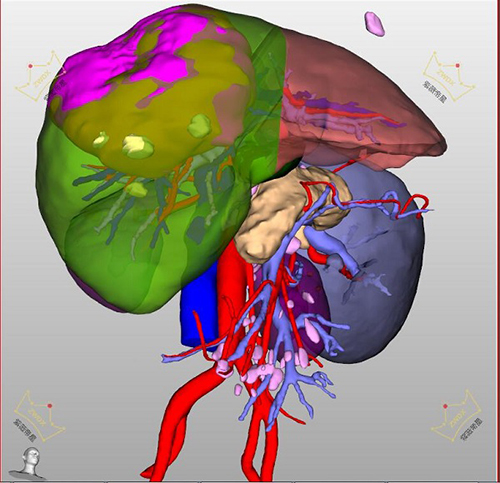

随后,患者在腹部肿瘤科经过详细的术前评估,利用三维重建CT技术,精准计算出患者标准肝脏体积1241毫升,预切线左侧肝脏体积505毫升,尾状叶36.2毫升,预留肝脏体积大于43.5%,评估残肝体积可以实现代偿。

患者肝部三维重建影像图